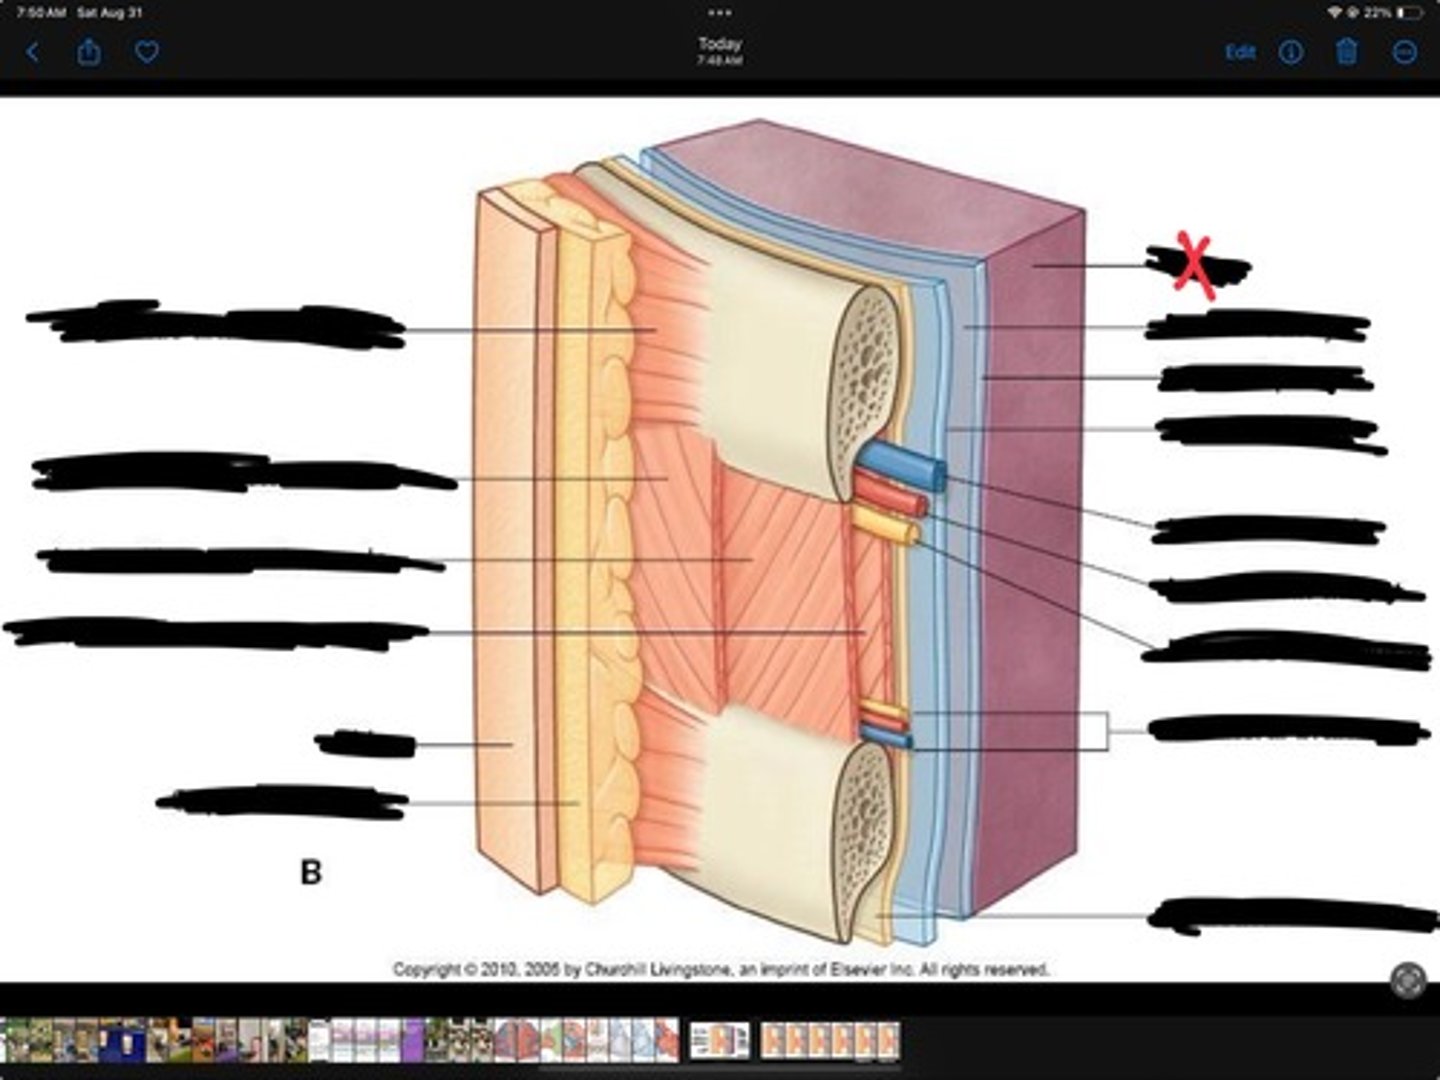

Innermost intercostal muscle

Skin

Internal intercostal muscle

External intercostal muscle

Serratus anterior muscle

Lung

Pleural cavity

Visceral pleura

Parietal cavity

Intercostal vein

Intercostal artery

Collateral branches

Intercostal nerve

Endothoracic fascia